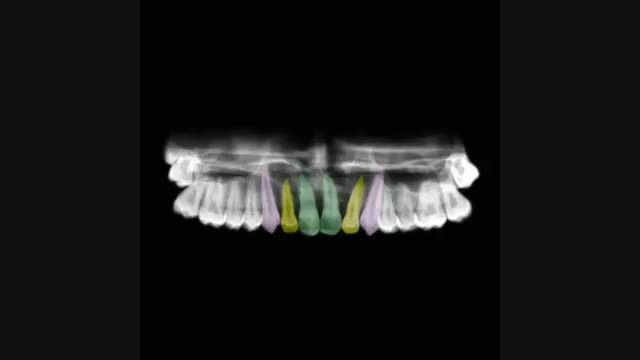

خارج کردن دندانهای شماره یک نهفته بیماری که کاملا به صورت افقی قرار گرفته بودند، توسط ارتودنسی ثابت پس از برداشتن دندانها اضافی که عامل نهفتگی آن دندانها بودند.